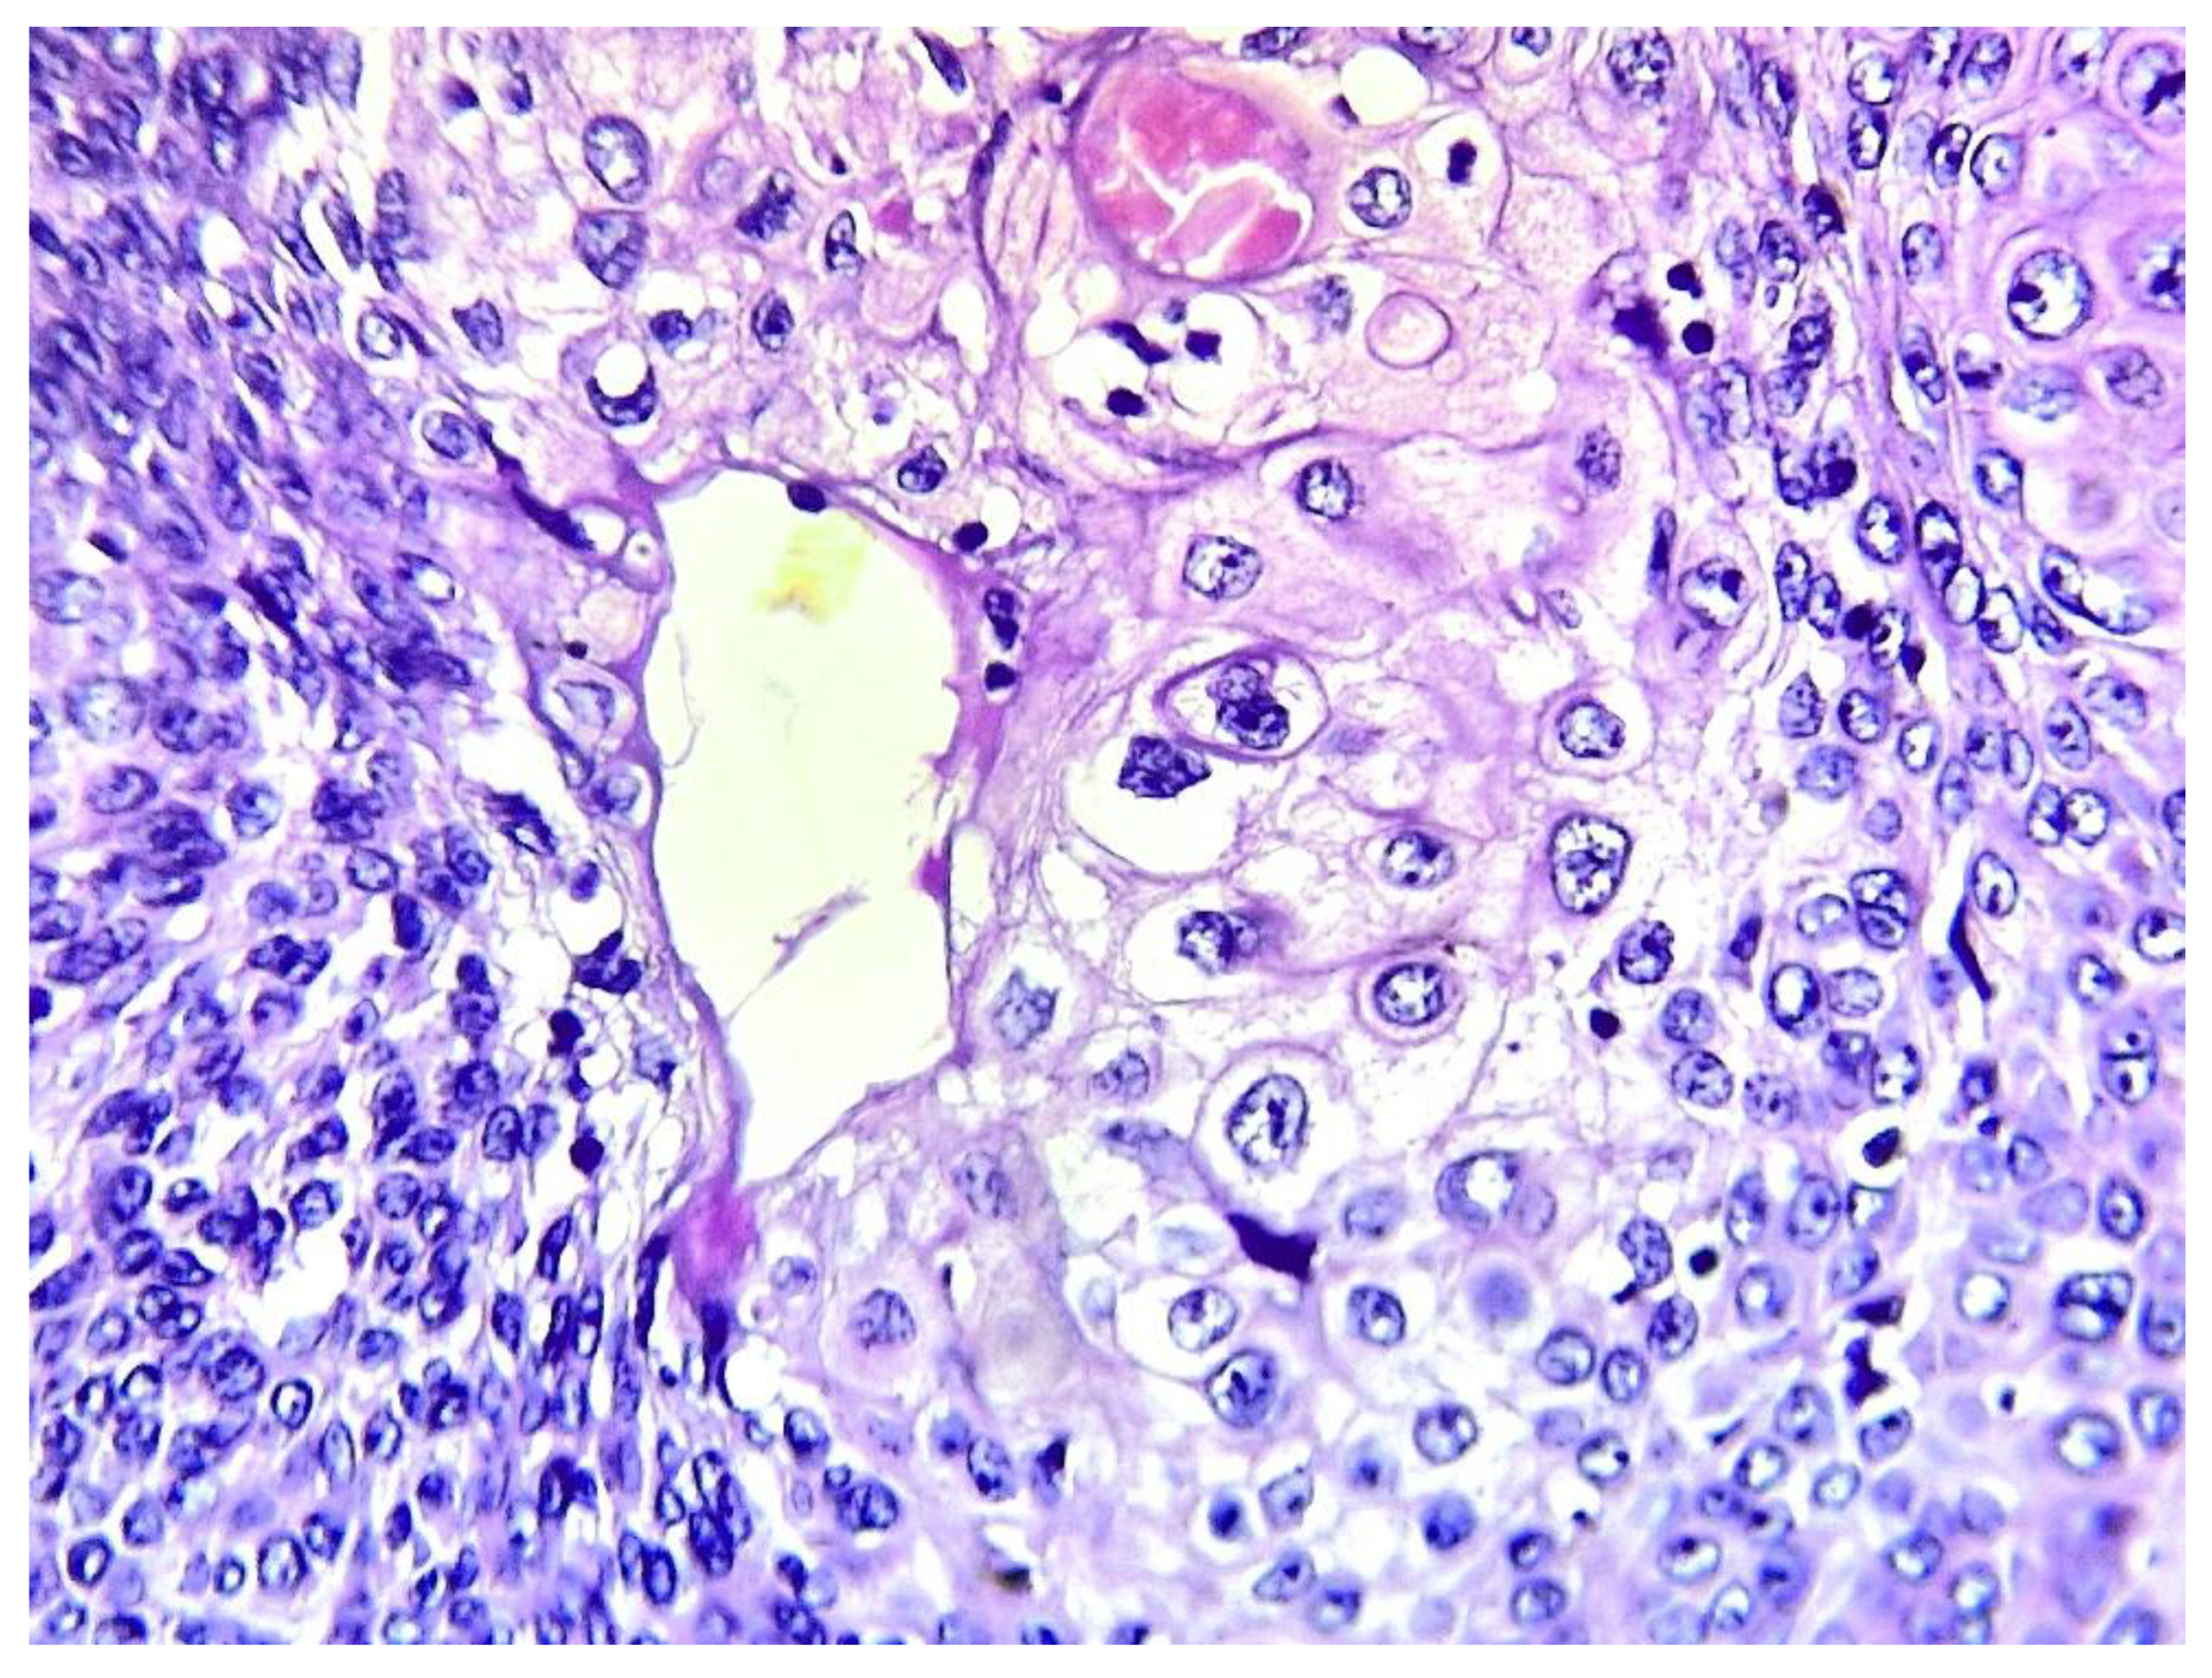

Sebaceous differentiation (Figure 7) and melanin pigments (Figure 8) were present respectively in 2 and 1 patients. Despite serial additional cuts, follicular or necrosis en masse, have not been found in all the 13 cases of the current series.

Figure 7. Sebaceous differentiation consisting of large cells with abundant clear granular cytoplasm with central rounded nuclei (hematoxylin-eosin x 400) (case 9).